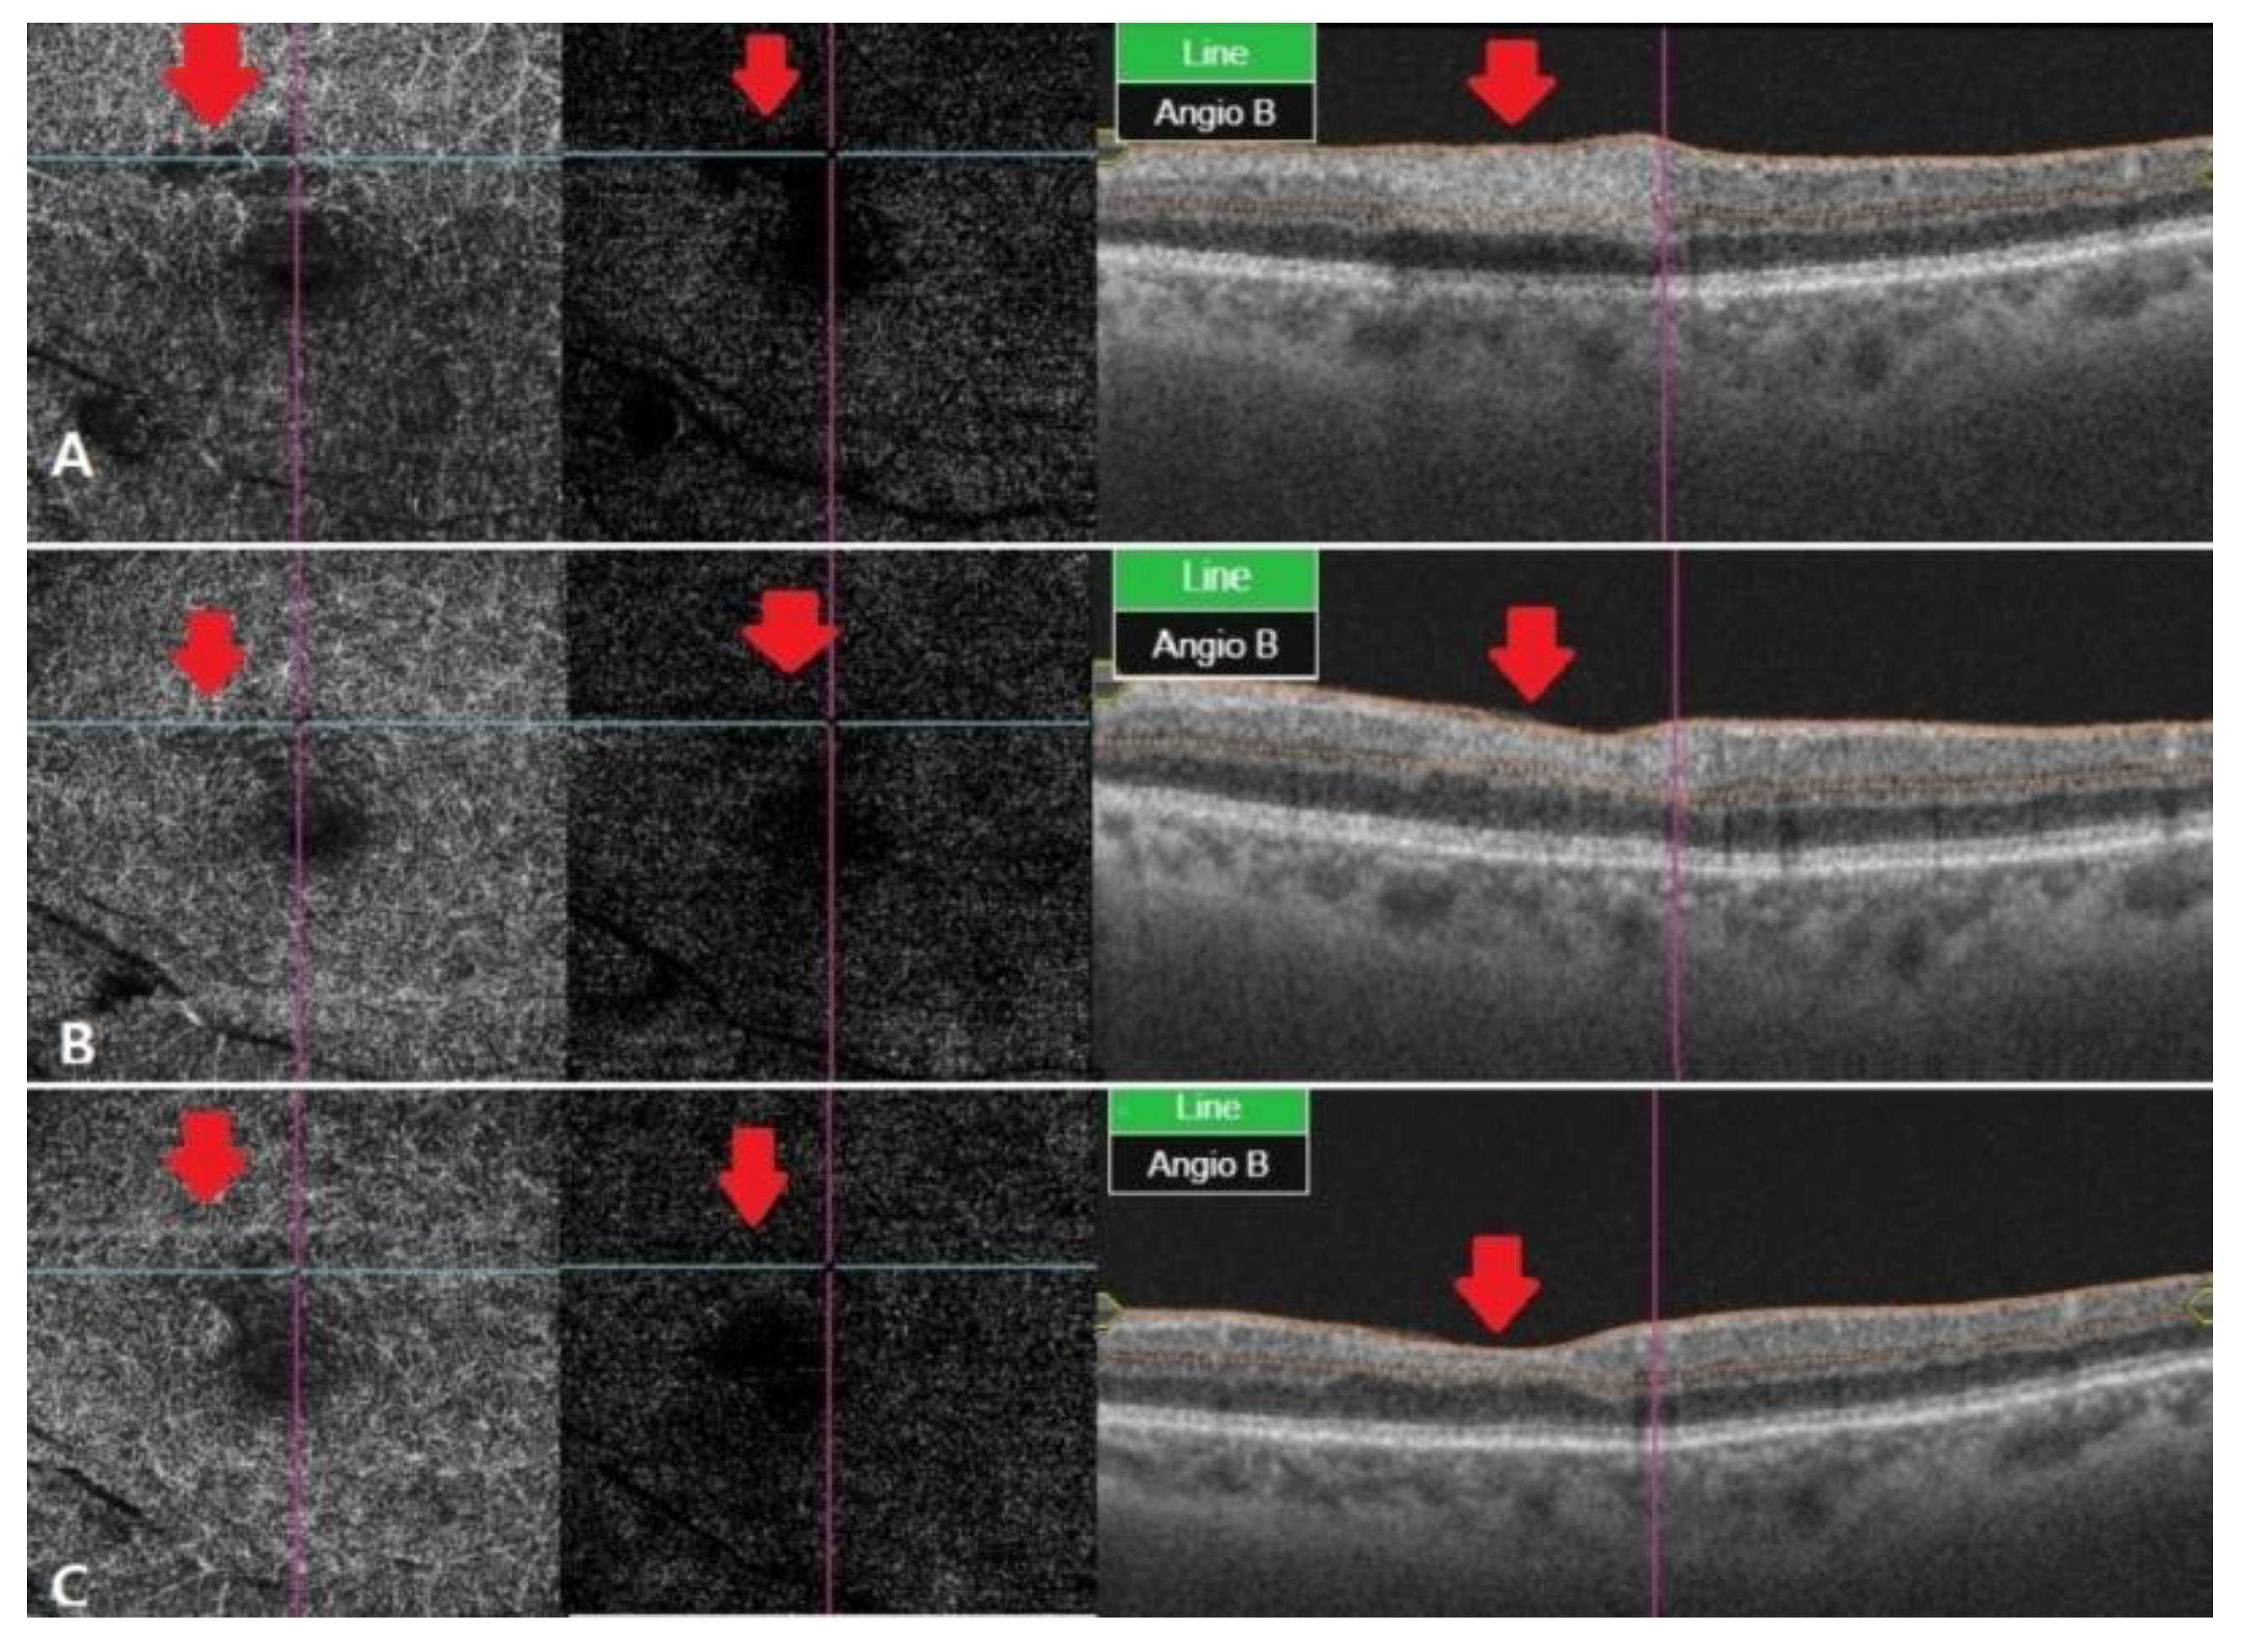

Figure 3.

OCT angiography at different stages of RAO. (A) After two weeks, OCT angiography was observed with vessel damage and window defect in deep and outer retina. (B) After a month, OCT angiography showed recovered vascular damage of deep and outer retina. This seems to be due to reperfusion and reduced window defect. (C) Two months later, deep and outer retinafully recovered in vascular findings. The macular window defect in the choriocapillaris area seems to be due to underlying drusen and PED.